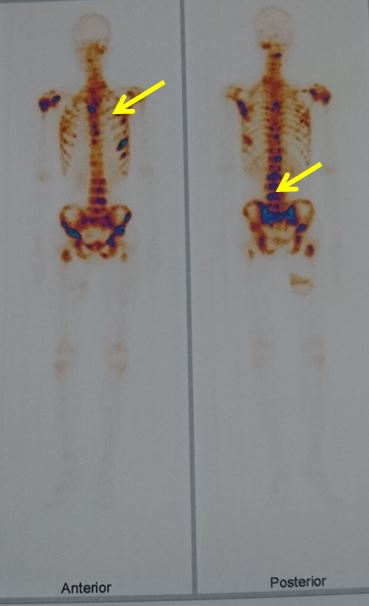

- Xạ hình xương: Tổn thương di căn xương đa ổ

Hình 3: Hình ảnh tổn thương xương đa ổ qua xạ hình xương

Hình 5: Kết quả xạ hình xương sau hóa trị số lượng tổn thương xương giảm, những tổn thương còn lại giảm độ tập trung hoạt độ phóng xạ.